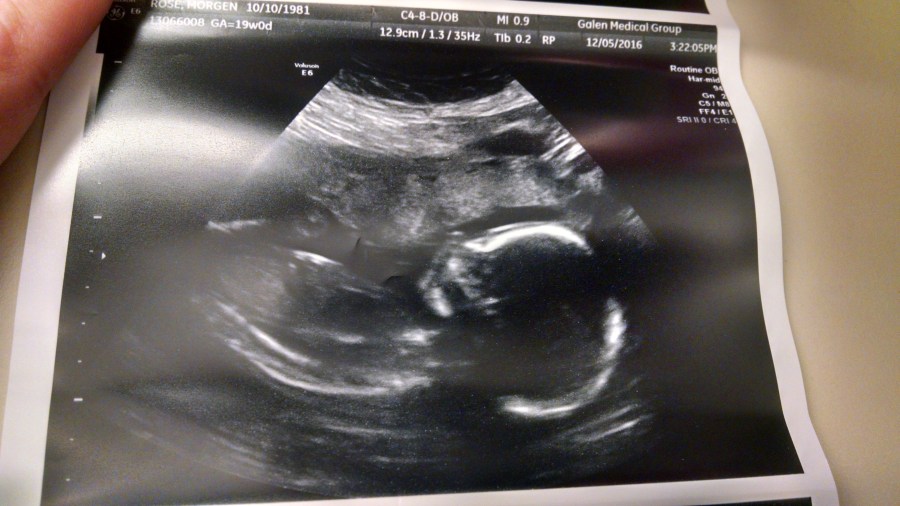

Turns out Little Ember wasn’t interested in being very helpful yesterday for her anatomy scan and was turned around (transverse=lying sideways) so there was a long (and pretty uncomfortable) process of trying to get all the photos they needed for measurements. She’s also hanging out pretty low, which means that most of the fun time was spent cramming the ultrasound wand right next to my hip bone in a generally painful way for about 45 minutes.

When we met up with my doctor, she congratulated me on having not gained much weight (2lbs so far!) but said that kiddo wasn’t being as helpful today. She walked us through the majority of the photos they got, saying “man, these aren’t great” – but reassured me that everything they saw looked exactly right, just that they weren’t able to look at everything. We heard the heartbeat and measured things like legs, arms, etc and looked at major organs. She said that we’d do another scan at 28 weeks, but that overall because of my earlier DNA scans, she wasn’t worried about anything. It was just inconvenient. I told her I expected this was only the beginning of my child not doing things the way I wanted her to, and we laughed.

Only one shot even KIND OF turned out, so here she is – 9 oz of tiny person.